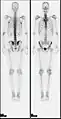

A nuclear medicine whole body bone scan. The nuclear medicine whole body bone scan is generally used in evaluations of various bone-related pathology, such as for bone pain, stress fracture, nonmalignant bone lesions, bone infections, or the spread of cancer to the bone.